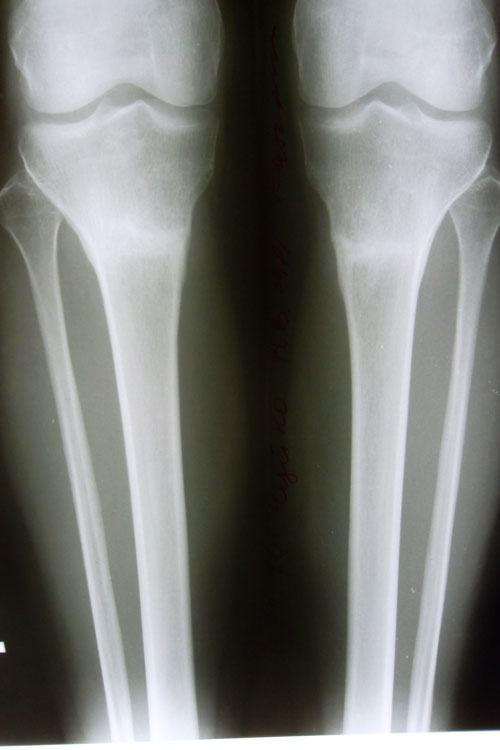

5 месяцев после снятия аппаратов.

- Диагноз: О-образная деформация ног

Господи, неужели это мои ножки?! Не верится, не устану говорить СПАСИБО Вам большое!Sekretar Onipko писал(а):Через 5 месяцев после снятия аппаратов!

Я веду практически обычный образ жизни, как до ОП. Уже практически 7 месяцев со дня снятия аппаратов, я ношу все что хочу, хожу быстрым шагом иногда, если тороплюсь, даже немного пробежаться могу. Бывает ножки ноют, когда стою долго на них, но это и на здоровых ногах бывает, намажу их гелем и утром все в порядке.